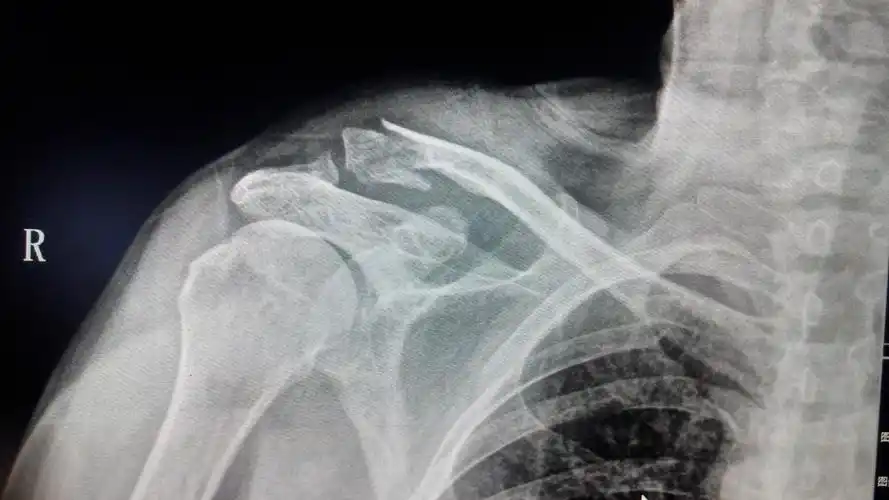

左锁骨肩峰端骨折